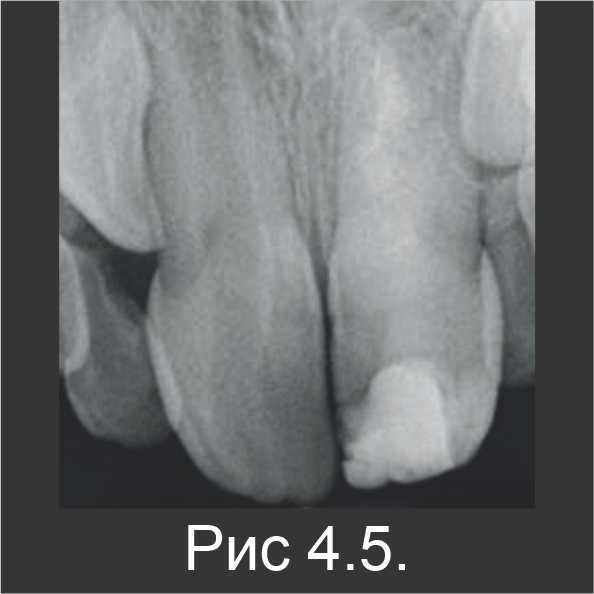

В ходе следующего посещения гидроксид кальция заменили материалом Biodentine™ (рис. 4.3). С помощью контрольного рентгенографического обследования, выполненного через 6 (рис. 4.4) и 18 месяцев (рис. 4.5), установили, что апексогенез зуба 21 продолжается и является сопоставимым с зубом 11, который не лечили (рис. 4.6).